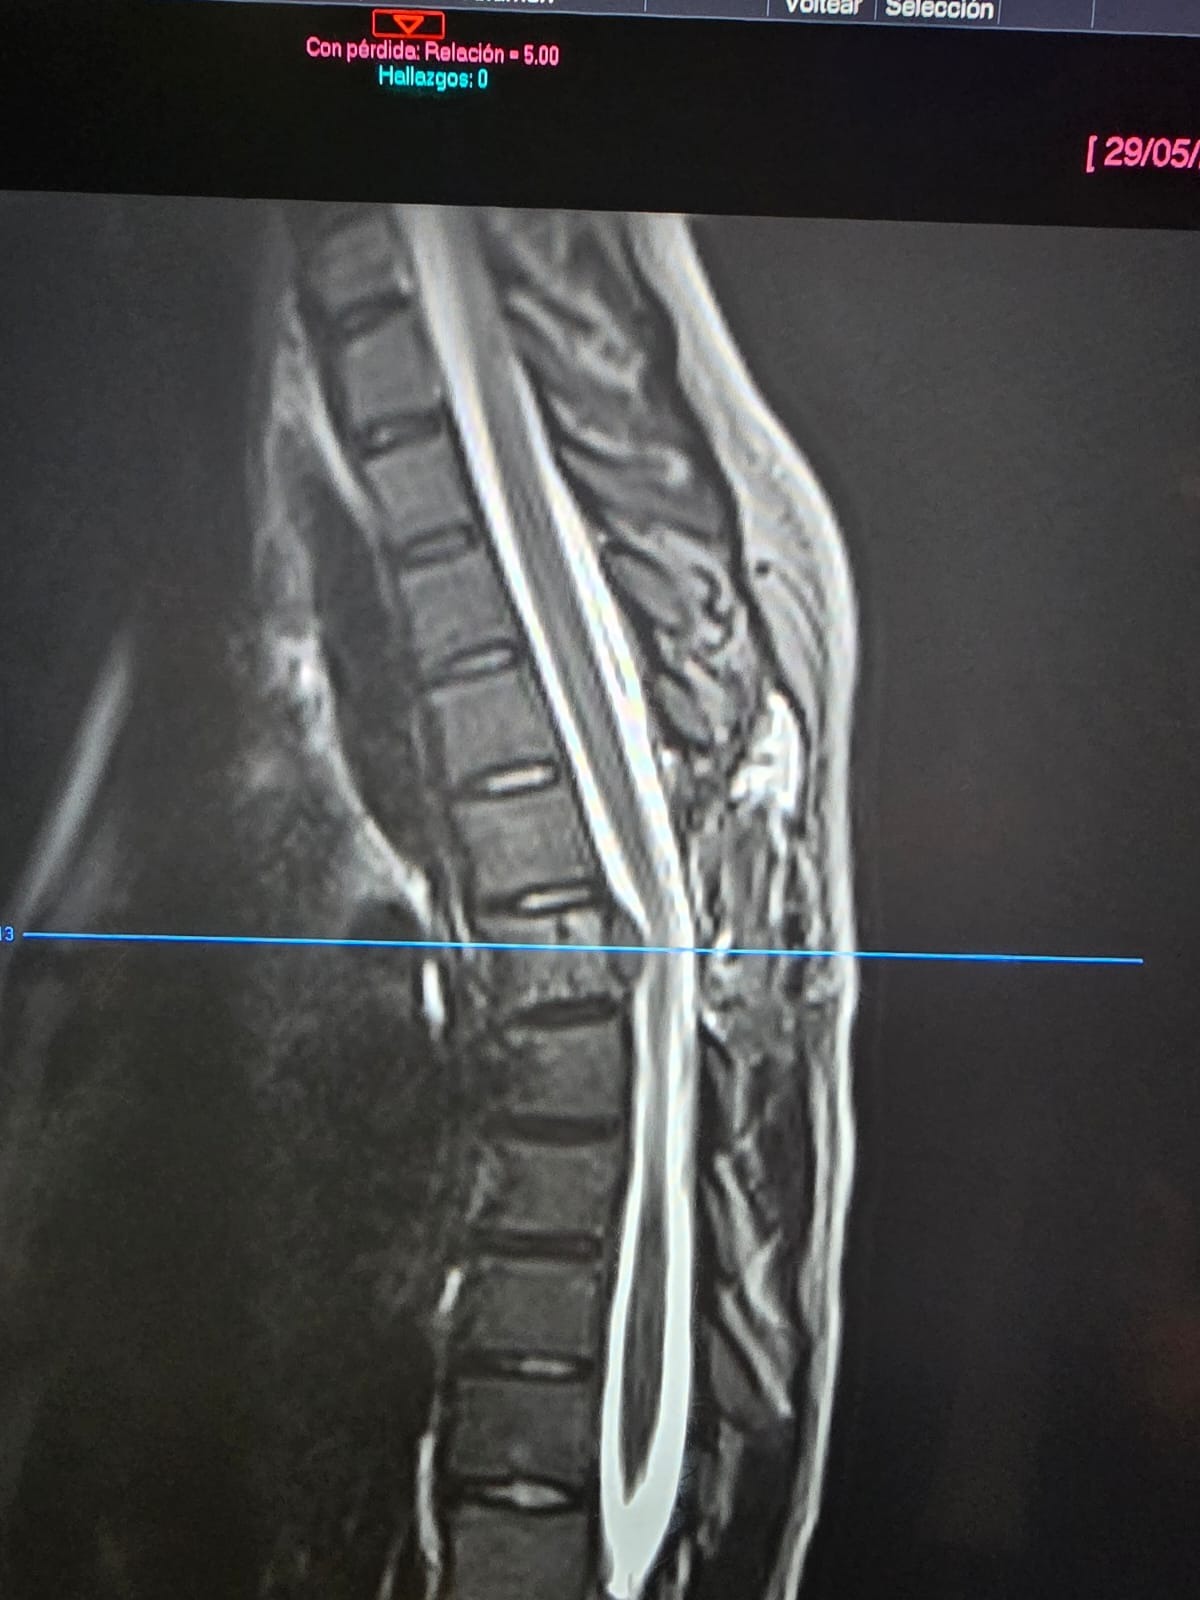

Nuestra pequeña guerrera, Marcelita, tuvo que someterse a una operación debido a un tumor en la columna, le diagnosticaron sarcoma de Ewing.